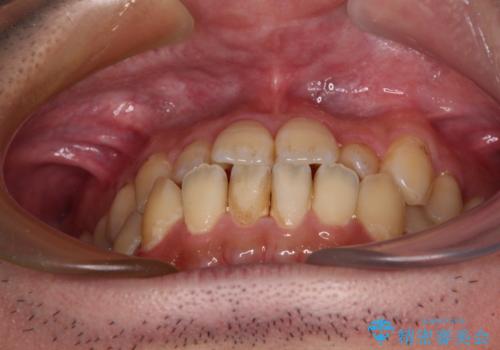

- 前歯のデコボコとクロスバイトを治したいとのことで来院された患者様です。

上下顎ともに歯列全体の側方拡大とIPR(歯と歯の間を削る)によってデコボコとクロスバイトが解消するように設計し、インビザラインにより治療を行うこととしました。

反対咬合特有の治療途中の前歯の干渉が長く続き、治療中に食事をとりにくく、ご迷惑をおかけしました。

前歯の咬み合わせの調整などを行い、安定した咬み合わせに仕上げることができました。